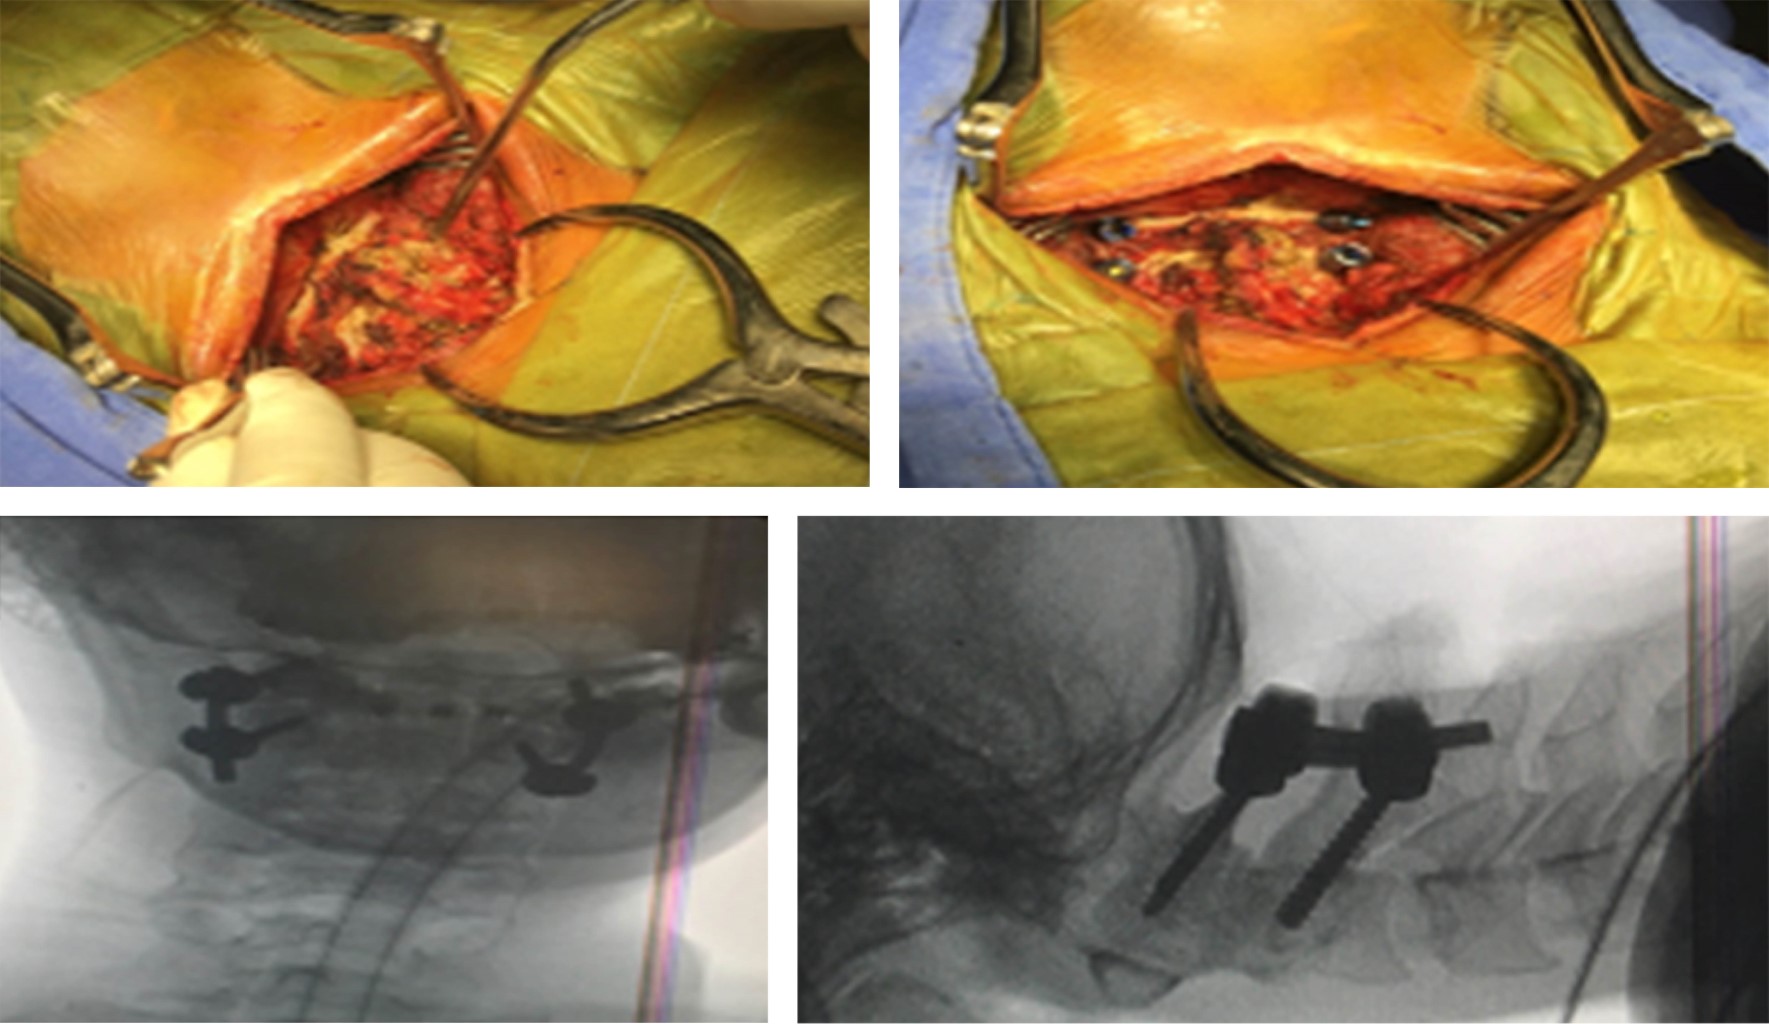

La cirugía fue el tratamiento primario en 20 pacientes (69%), con abordaje anterior en 37.93% (11 pacientes) y abordaje posterior en 31.03% (nueve pacientes). Por lo general, se prefirió la cirugía anterior en pacientes con líneas de fractura oblicua posterior u horizontal, dolor local y una superficie de contacto entre la odontoides y el cuerpo de C2. Se eligió un abordaje posterior cuando la distancia entre los fragmentos óseos fracturados fue > 2 mm, conminución o que existiera alguna asociación que requiriera estabilización posterior Se realizó un abordaje 360 (tornillo cervical anterior e instrumentación posterior) en un paciente (3.45%) que presentaba inestabilidad posterior además de una línea de fractura odontoidea horizontal.

El tratamiento conservador fue el tratamiento primario en nueve pacientes (31.03%), utilizando principalmente collarín rígido tipo Philadelphia y el inmovilizador occipito-esternomandibular (collarín SOMI), así como en algunos casos el halo-chaleco. El tratamiento quirúrgico fue elegido como tratamiento en 68.97% (20 pacientes). Se realizó el abordaje anterior utilizando un tornillo odontoideo interfragmentario en nueve pacientes (31.03%) (Figura 3). Se realizó una instrumentación posterior en 37.93% de los casos (10 pacientes). La mortalidad asociada fue de 17.2% (cinco pacientes) (Tabla 1).

El manejo para las fracturas de odontoides tipo II se puede dividir en dos grandes grupos, conservador y quirúrgico, este último se divide en dos abordajes en general.12 La primera opción es el abordaje anterior con la colocación de uno o dos tornillos odontoideos interfragmentarios, el cual se describe como la técnica de elección en la mayoría de las fracturas Anderson y D'Alonzo tipo II, siendo en específico los subtipos de acuerdo con la clasificación de Grauer IIA y IIB.13 El manejo quirúrgico con abordaje posterior se debe realizar de la mano con una reducción cerrada previa colocación de un halo cefálico y al igual que el tornillo odontoideo, control imagenológico transquirúrgico, realizando la instrumentación posterior C1-C2 dependiendo del tipo de trazo y el desplazamiento que se presente.14 Ambos abordajes son un recurso que, si bien cuenta con indicaciones específicas, es a elección del cirujano quien realizará un abordaje anterior o tras la valoración integral del paciente optará por un abordaje posterior al presentar algún dato de inestabilidad, o que tras la osteosíntesis anterior pudiera presentar una insuficiencia de la reducción y estabilidad.15,16

Figura 3